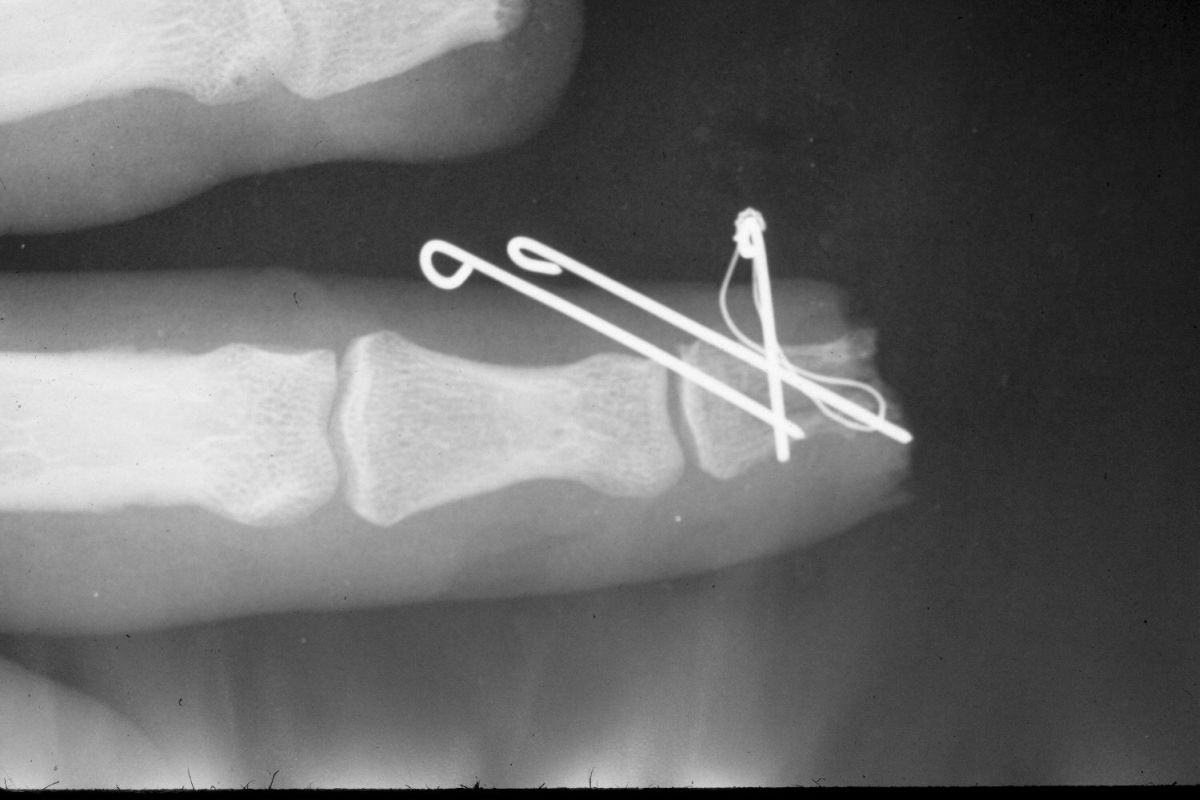

| Distal phalanx

fracture stabilization. Pins were placed to protrude

proximally in anticipation of flap cover. |